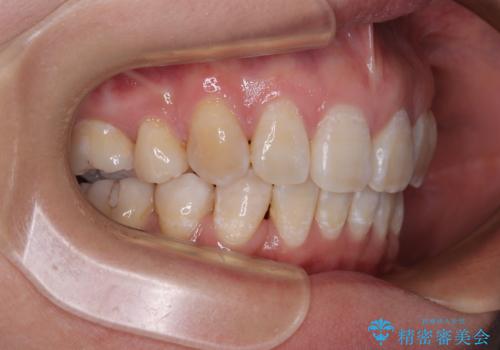

- 上顎歯列の出っ歯を気にして来院された患者様です。

骨格的に上顎歯列が前方位にあり、口元の突出感が顕著な状態で、上下左右の第一小臼歯4本を抜歯して、ワイヤー装置での抜歯矯正を行うこととしました。

ご本人がびっくりするくらい劇的に口元の突出感が改善され、大変満足のいく仕上がりとなりました。